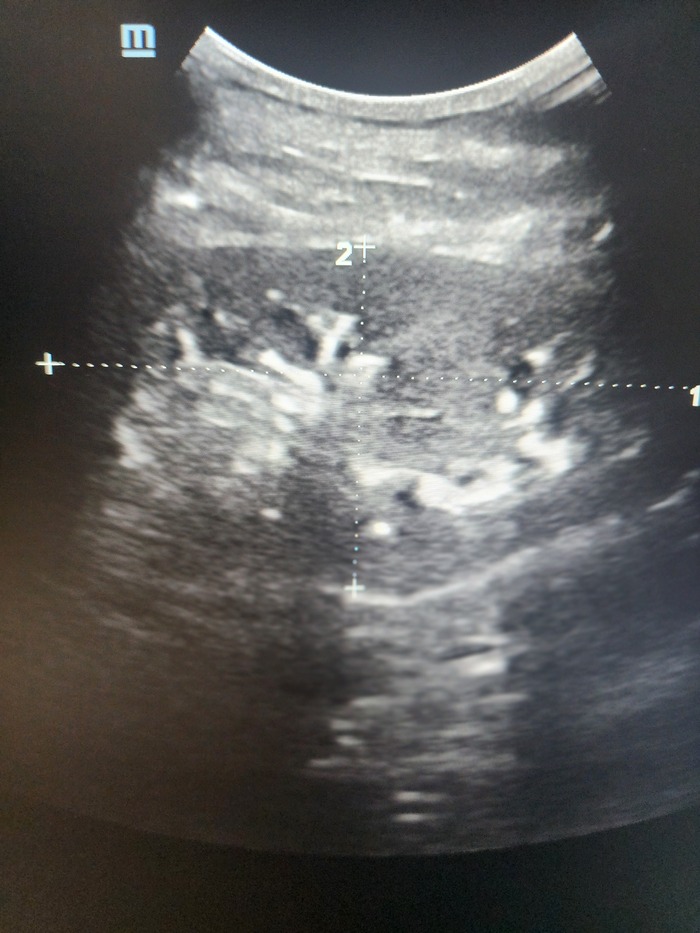

Часто ко мне на приём приходят пациенты с жалобами на боли в коленном суставе. Боли появились беспричинно, сначала были слабыми и не постоянными, потом усиливались и стали беспокоить практически все время, даже ночью. Смотрю МРТ, там стандартные дегенеративные изменения в менисках и хряще, то есть картина артроза или остеоартрита, если говорить современным языком. Это все лечится консервативно за счет определённой комплексной терапии, которая подбирается индивидуально под пациента с учетом многих факторов. НО!

Но это всё лирика, теперь факты. Проведено обширное исследование с участием более 1200 пациентов, доказывающее отсутствие каких либо преимуществ артроскопии коленного сустава при дегенеративных изменениях менисков и хряща перед консервативной терапией. И это без учета рисков оперативного вмешательства.

Артроскопия - классная современная операция, но это именно операция. Мы к ней прибегаем, когда другие методы неэффективны или нецелесообразны. Например, она необходима, когда мы видим четкие разрывы менисков, вызывающие боли и блокады в суставе, разрыв крестообразной связки с нестабильностью сустава, когда в суставе есть хондромное тело, нарушающее его функции. НО НЕ С ЦЕЛЬЮ ПОЧИСТИТЬ/ПОГЛЯДЕТЬ!!!